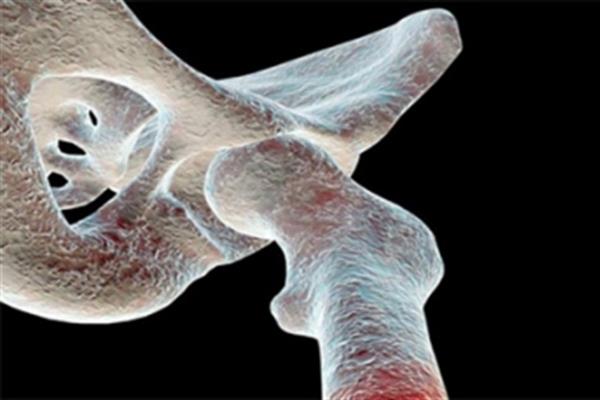

Explicó que la resistencia de un injerto, cuña, lámina o membranas de hueso de caballo, en cualquier parte del sistema óseo humano, puede soportar hasta 300 kilogramos de pesos.

Por su parte, el especialista en estos procedimientos, el doctor Jorge Alberto Ponce García, detalló que el implante de equino sirve para realizar correcciones de pie plano, cuñas para rodillas, columnas y pómulos.

Manifestó que el hueso de equino, tratado mediante un proceso biotecnológico de “desantigenización enzimática”, se puede implantar en cualquier parte ósea del cuerpo humano.

El especialista indicó que una gran parte de los casos atendidos en este país son por fracturas, particularmente de la cadera, en adolescentes y personas de la tercera edad.